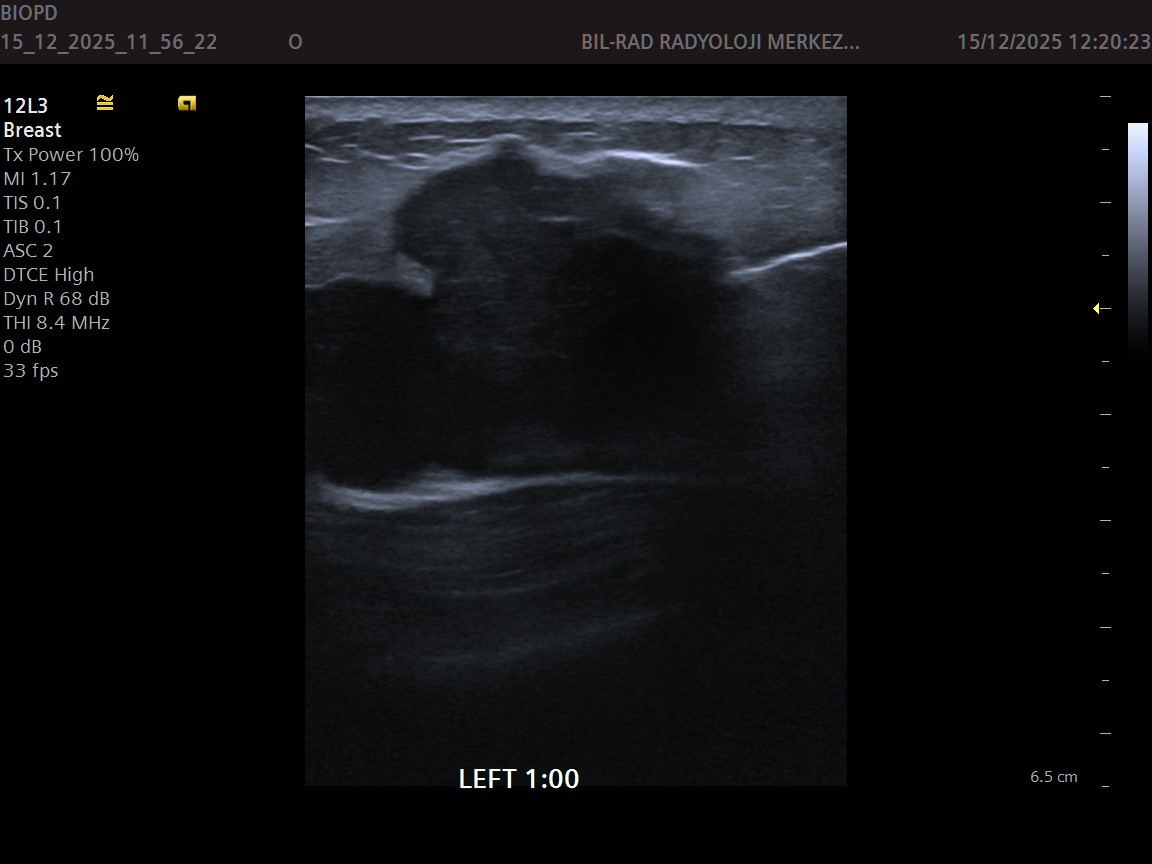

Ultrasonografi yaygın klinik kullanımı ve gündelik sorunlara pratik çözümler sunan bir modalite olmakla birlikte elde edilen bulgular hem uygulayıcıya bağımlı hemde kullanılan cihazın teknik özellikleri ile ilişkilidir. Merkezimizde 2024 model Siemens Acuson Juniper cihazımızla 20 yıldan fazla tecrübeli Avrupa radyoloji Diplomasına sahip (EDIR) hekimlerimiz tarafından incelemeleriniz yapılır. Merkezimizde her hastaya yeterli zaman en az 20 dk ayrılarak detaylı incelemeler gerçekleştirilir.

Meme Ultrasonografisi